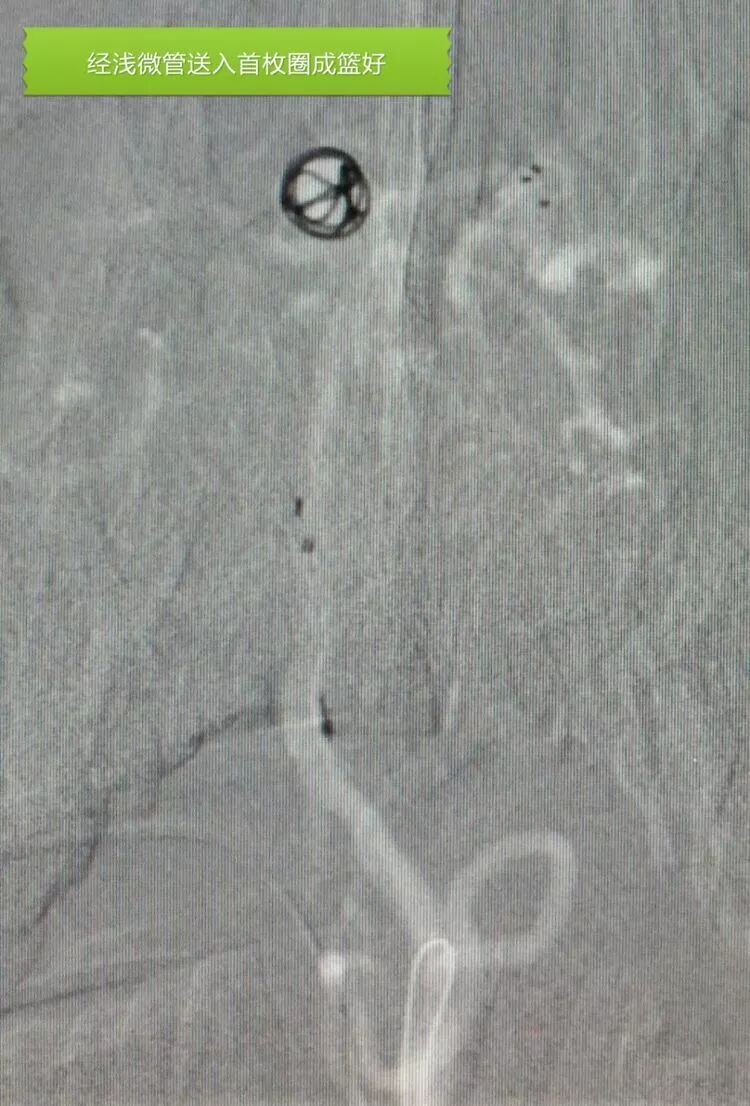

应用Solitaire支架结合双微管栓塞,一根微导管是45°预塑形的,管头置于瘤体中央(浅管),另一根微导管管头塑成C形,沿瘤底深入到瘤体右侧角(深管)